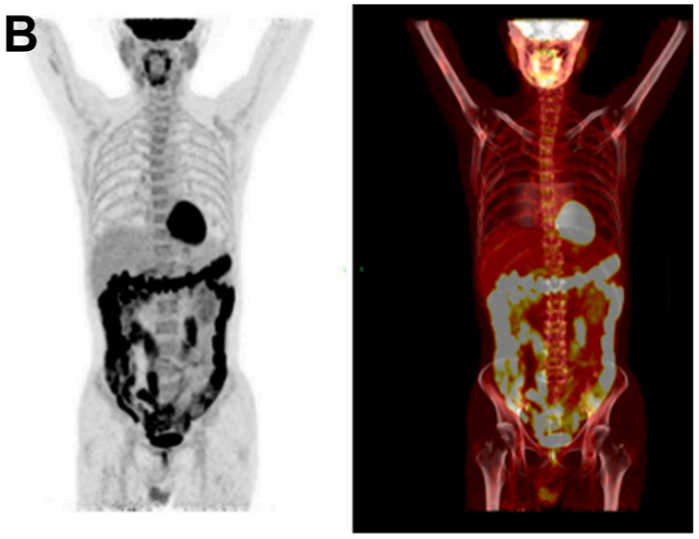

腹泻3年+小肠溃疡+黏膜萎缩,大剂量泼尼松治疗无效,这种极易漏诊的罕见病如何破局?

病史摘要:63岁男性患者,有3年慢性腹泻史,近期加重,每日排便4 - 8次,伴体重减轻5kg。诊疗过程:查体见消瘦、肠鸣音亢进,BMI 16.4kg/m²。实验室检查有多项异常,腹部CT见腹膜后血管迁曲及肠系膜淋巴结肿大,结肠镜示右半结肠炎,PET - CT示结肠炎症和轻度高代谢淋巴结,小肠镜见多发溃疡等。排除乳糜泻等疾病,血清蛋白电泳提示M蛋白水平升高。初始经验性治疗效果不佳